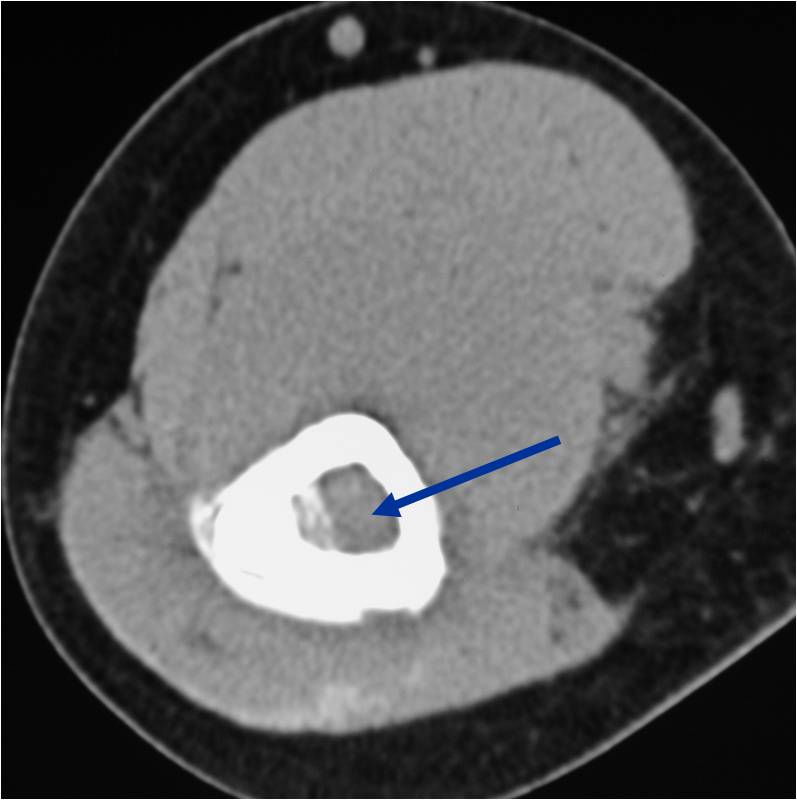

- Soft tissue mass— by CT (80%); by MRI (100%)

- Sequestra (16%)

Permeative Lesion